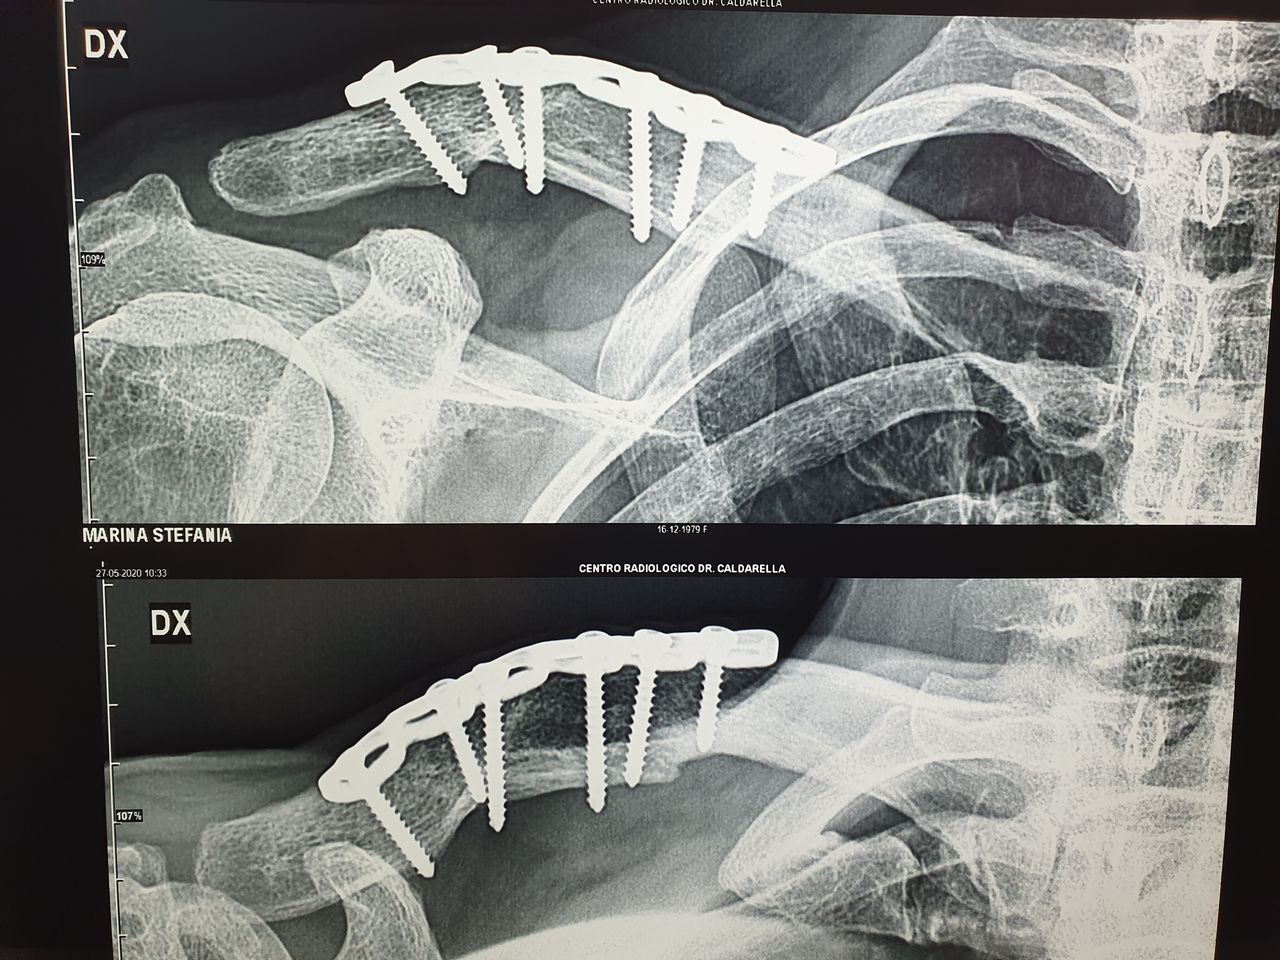

CHIRURGIA DELLA MANO:

* Neurolisi (Sindrome del Tunnel Carpale), Tenolisi (Dito a scatto, Sindrome di De Quervain), Morbo di Dupuytren

(trattamento percutaneo)

* Protesi della Trapezio Metacarpica (Rizoartrosi)